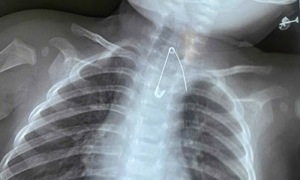

Yingjie, 51, experienced a persistent cough, shortness of breath, and dull chest pain. Doctors discovered a mass in his mediastinum and another in the upper lobe of his lung.